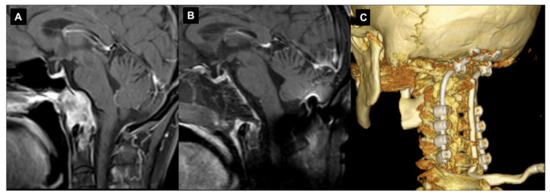

However, one of the potential complications of the transclival–transodontoid EEA is the postoperative instability of the CVJ (Figure 5).

Figure 5.

Endoscopic endonasal approach to CVJ chordoma and occipitocervical fixation. Sagittal preoperative (A) and postoperative (B) T1-weighted MR images after contrast injection showing the chordoma infiltration of C0-C1-C2 complex joint and a gross total resection. In the same surgical setting, an occipitocervical fixation was performed. A 3D reconstruction of the postoperative CT (C).

This can occur when the stability of the CVJ is compromised by the surgical procedure or preoperatively by tumor growth, which leads to symptoms such as neck pain, weakness and spinal cord compression. The risk of postoperative instability can be reduced by careful preoperative planning, proper surgical techniques and appropriate postoperative management [107]. There are several different techniques that have been used to prevent instability after the EEA. These include the use of internal fixation devices such as screws and rods in the pre- or immediate postoperative course, as well as the use of external fixation devices such as halo traction. There have been several studies published in recent years that have investigated the incidence and management of postoperative instability after applying the EEA for CVJ tumors, with a focus on condyle resection. An anatomical study showed that a lower-third clivectomy and unilateral anterior condylectomy through an EEA can cause progressive hypermobility at the CVJ. On the basis of biomechanical criteria, OCF is indicated for patients who undergo a > 75% anterior condylectomy [108]. Kooshkabadi et al. evaluated the incidence of postoperative instability after an EEA for CVJ tumors. The study included 212 patients who underwent an EEA for lower clivus lesions, and they found that around 3.3% of the patients required a fixation. They showed that an EEA resection greater than 75% of the occipital condyle significantly increased the risk of CVJ instability, which required subsequent fixation. The degree of the condyle resection was a significant factor that predisposed it to the occipitocervical instability [109]. There are also some reports, mainly related to the EEA to CVJ abnormalities and basilar invagination, on the preservation of the anterior C1 arch that avoids the need for posterior fixation with the aim of preserving the rotational movement at the C0–C2 segment and reducing the risk of a subaxial instability development [98,110,111]. Overall, these studies suggest that the entity of condyle resections, C1 anterior arch and transverse ligament preservation while using the EEA on CVJ tumors may represent two significant factors that are related to the risk of postoperative instability [107,112]. However, the evidence is not entirely consistent, and further studies with larger patient populations and longer follow-ups are needed to better understand the risk. The most consistent risk factor identified across these studies is the size and location of the tumors, specifically tumors located in the upper cervical spine and tumors with a wide base. Other factors that have been identified as risk factors for postoperative instability include the degree of resection, the surgical approach and the reconstruction methods used.